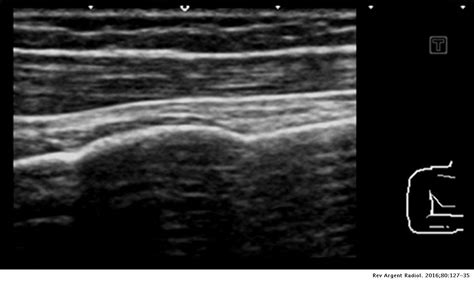

Ilustración de la perforación de la cortical ósea durante la anestesia transcortical.

- Segunda etapa: La perforación de la cortical ósea se efectúa a 2 o 3 mm de la línea de los cuellos anatómicos. En el maxilar, podemos situarnos entre 2 y 10 mm de la línea de los cuellos, en la vertical exacta del medio de la papila interdental. La perforación se efectúa siempre en perpendicular a la superficie de la cortical, y debe ser lenta para evitar cualquier calentamiento del hueso. No es conveniente, para ganar tiempo, apresurarse al perforar la cortical.

- Tercera etapa: La inyección de la solución anestésica, que se puede preceder de una leve retirada de la aguja para dejar al anestésico espacio para la difusión.